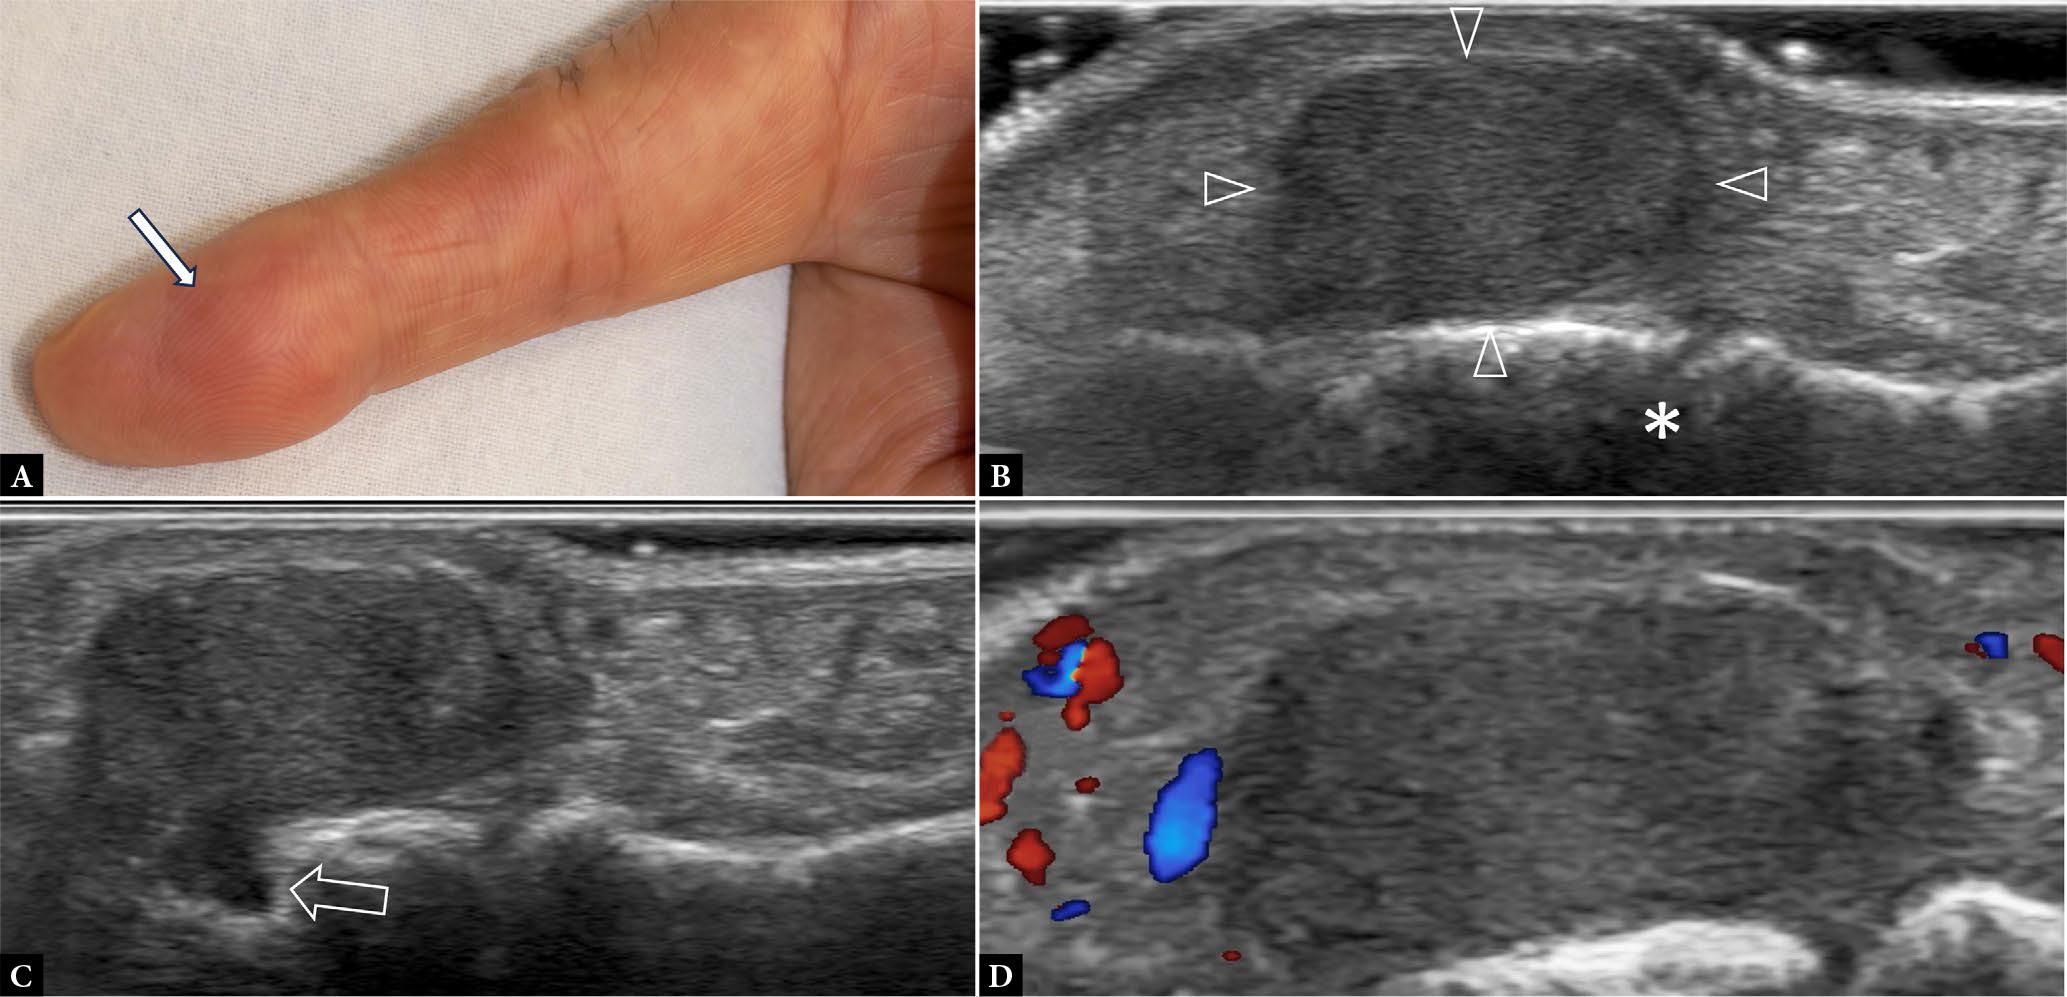

In most of the remaining cases, one will not be completely confident regarding the nature of the tumor following US examination, though one is still quite confident, based on the US appearances and clinical history, that the tumor is benign (Fig. 11). In such situations, the three most likely diagnoses in order of perceived likelihood can be listed, and, if the initial clinical suspicion was that of a malignant lesion, the US examiner should emphasize that the appearances favor a benign rather than a malignant tumor. Depending on location, the clinical context, and the patient’s response to being informed of the US findings, percutaneous biopsy, excisional biopsy, or MRI examination can be performed. If the patient refuses a biopsy or surgery, and MRI examination is not feasible, follow-up US examination is usually recommended at an appropriate time, usually in 3–6 months.

Fig. 11.

72-year-old male with painless lump in the apical pulp space of the index finger, which was slowly enlarging for one year. A. Clinical photograph shows the mass (arrow). Longitudinal B, C. greyscale and D. color Doppler US show a well-defined medium-sized mass (arrowheads) in the apical pulp space. The mass extends to, but does not definitely involve, the distal interphalangeal joint (DIPJ) (*). The mass seems to extend into a small cortical defect (open arrow) of the distal phalanx. No tumoral vascularity was evident. Overall, in view of possible intracortical extension, nerve sheath tumor was considered more likely than giant cell tumor tendon sheath (GCTTS) or glomus tumor. MRI and US-guided biopsy were recommended. MRI will help clarify the extent of the mass and possibility yield more information on the nature of the mass, such as hemosiderin deposition in GCTTS. Biopsy will help confirm the nature of the mass, which will help surgical planning